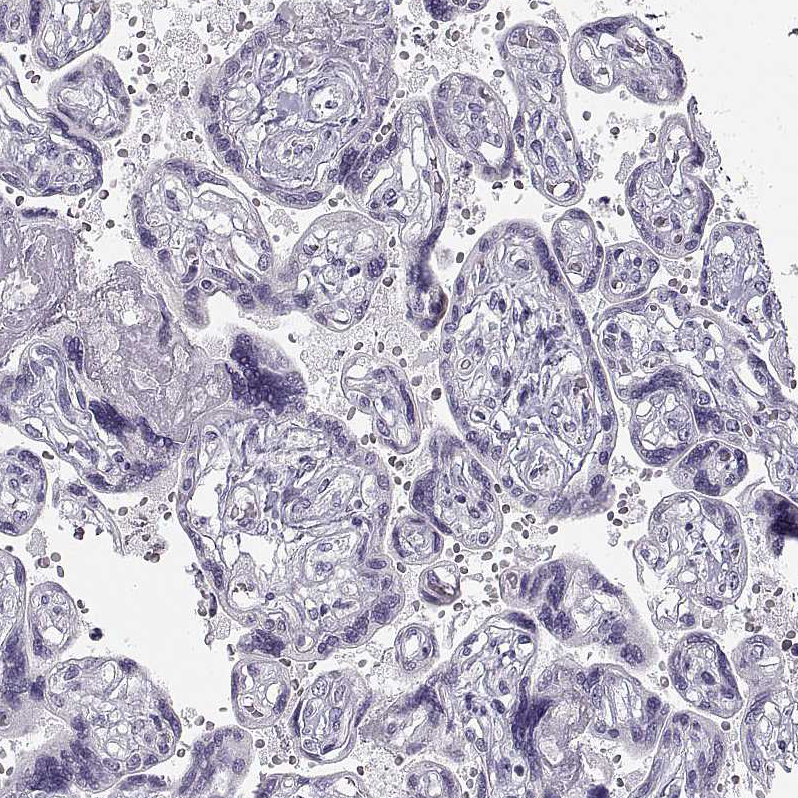

Learn how we validate our antibodies, how we secure their reproducibility, and why we apply enhanced validation. Our antibodies are validated in IHC, ICC-IF, and WB.